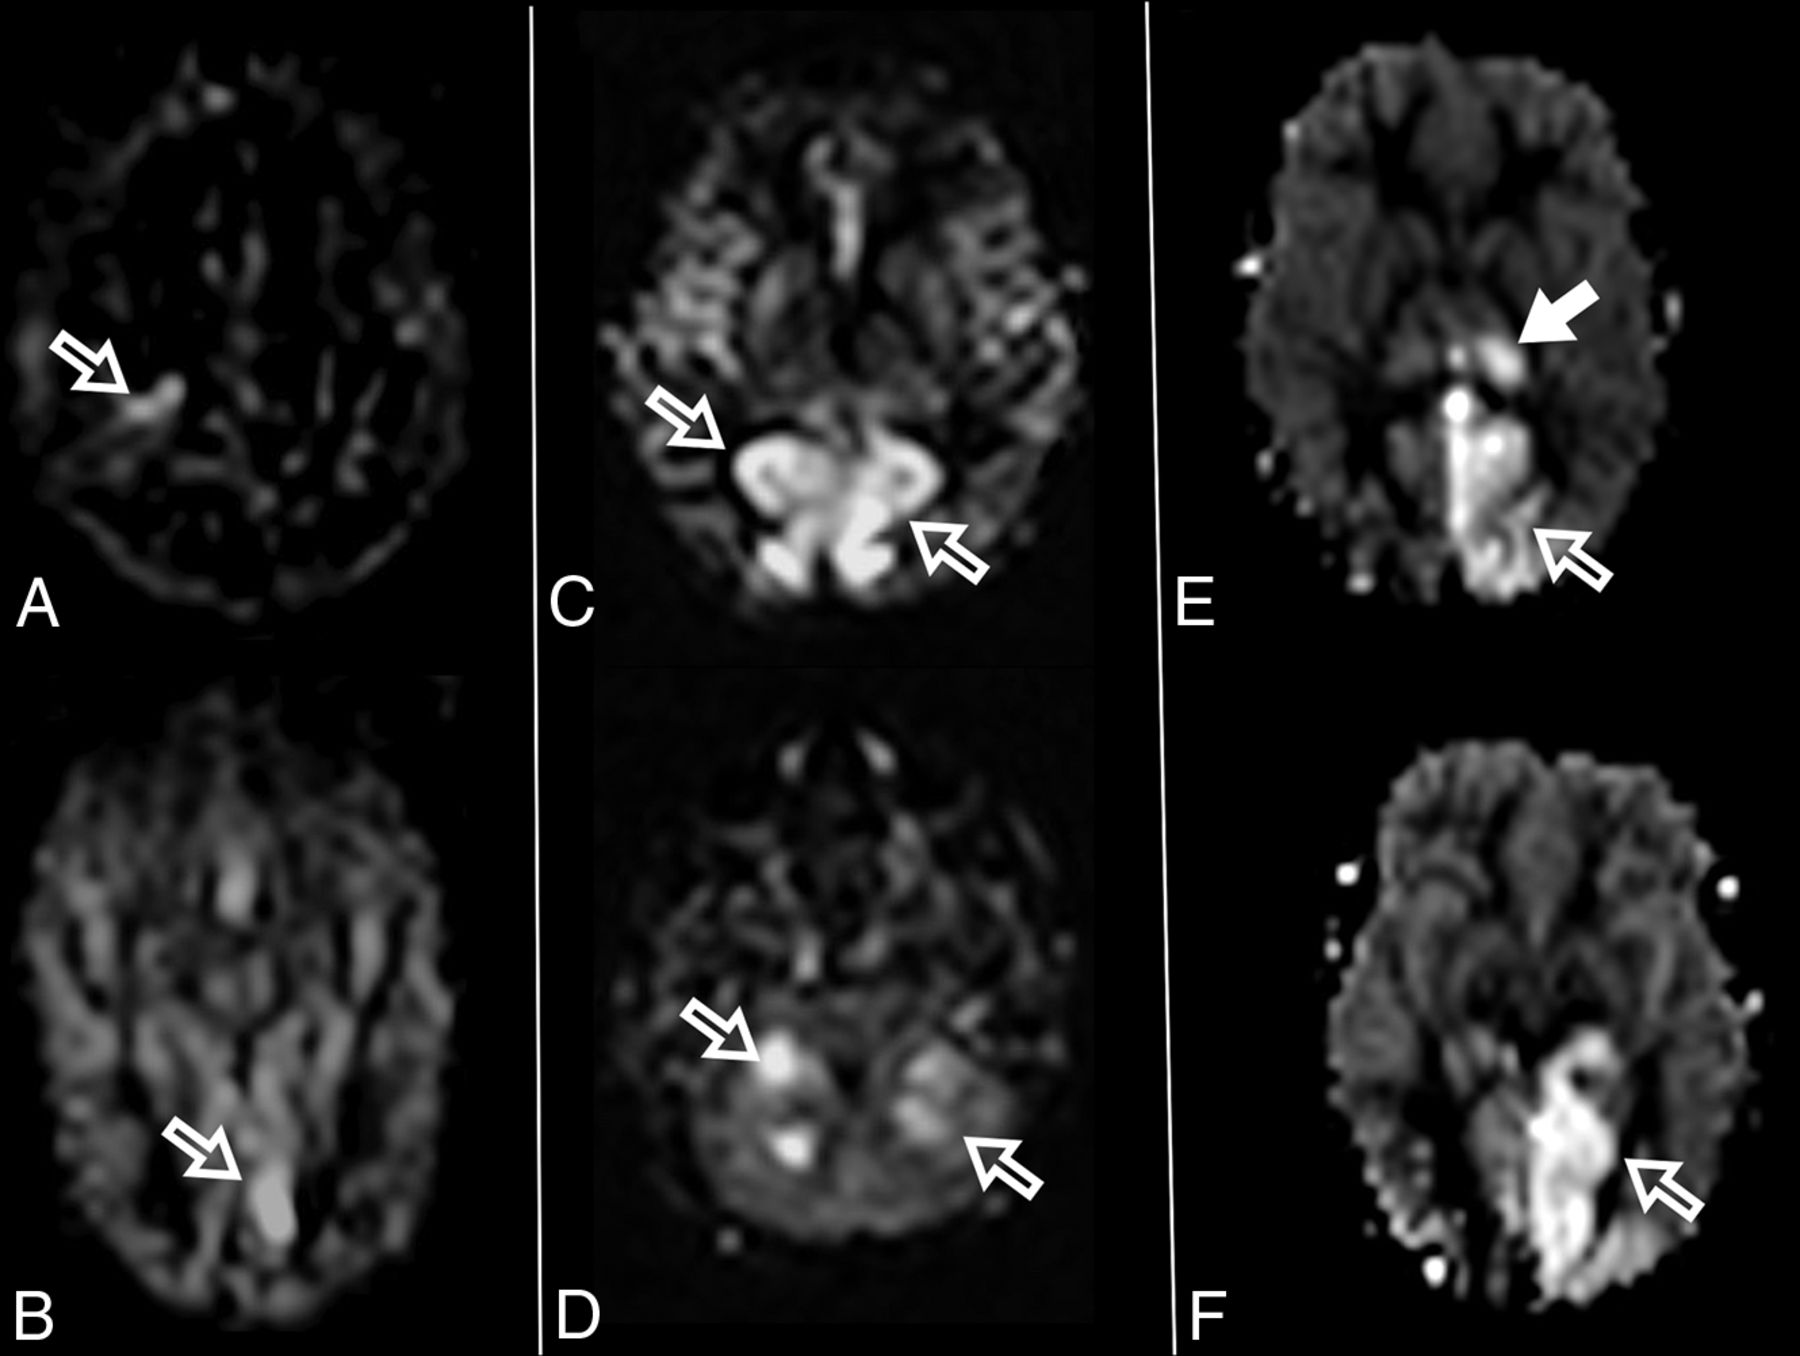

At diagnosis, brain MR imaging findings were abnormal in most patients (n = 12, 92%). The most common brain MR imaging findings were unilateral or bilateral perirolandic signal changes (n = 7, 54%) (Fig 1) and unilateral or bilateral thalamic signal changes (n = 10, 77%) (Fig 2). Perirolandic signal abnormalities were unilateral in most cases (n = 5, 71%) and were more frequently seen only affecting the precentral or both the pre- and postcentral gyri. Half of the thalamic changes were unilateral (n = 5, 50%). Simultaneous perirolandic and thalamic signal changes occurred in 6 patients (n = 6, 46%). An association of EPC (clinically/EEG) and perirolandic signal changes was present in 6 patients (n = 6, 75%), and an association of EPC (clinically/EEG) and thalamic signal changes, in 7 patients (n = 7, 87.5%). Two patients with EPC (clinically/EEG) did not present with perirolandic signal abnormalities. The findings positive for lesions overall were on the DWI of 10 patients (n = 10, 83%), on the T2WI of 9 patients (n = 9, 75%), and on FLAIR of 7 patients (n = 7, 58%). In 4 patients, DWI was the only sequence with abnormal findings. The occipital lobe was affected in the early brain MR imaging in 2 patients (n = 2, 15%). Signal changes in other brain regions were found in 5 patients (n = 5, 42%), involving multiple regions, namely the cerebral white matter, insula, putamen, caudate nucleus, fornix, cerebellar vermis, and also the frontal and occipital lobes. One patient did not present with either perirolandic or thalamic changes but instead presented with a diffuse pattern similar to that of leukoencephalopathy, with restricted diffusion in the white matter and white matter tracts (Fig 3). Three patients had an abnormally high lactate peak on MR spectroscopy. None of our patients had ASL or other perfusion-weighted imaging at the time of diagnosis. T1 and T2* imaging and SWI had negative findings at the time of diagnosis.

MR imaging thalamic signal changes in 3 different patients with POLG-related disorders (A, A 9-month-old female), (B, A 3-year-old female), and (C, A 3-year-old male). Thalamic signal changes were also variable with varying degrees of conspicuity. A, DWI. Signal changes were subtle and focal with restricted diffusion in the right thalamus (open arrow). B, FLAIR. Signal changes involved both thalami, more conspicuous on the left side (open arrows). C, T2WI. Signal changes were bilateral and symmetric involving both thalami (open arrows).

Thalamic signal changes were also frequent at the time of diagnosis and on follow-up imaging. Unilateral or bilateral thalamic involvement was identified in most patients during the onset of their disease. In our cohort, there was no new thalamic involvement at follow-up. On follow-up imaging, thalamic changes had different outcomes: complete resolution, progression from unilateral to bilateral involvement, progression accompanied by volume loss, and fluctuation with periods of an almost-complete resolution and frank progression. Thalamic signal changes were variably detected on DWI, T2WI, FLAIR, or ASL.